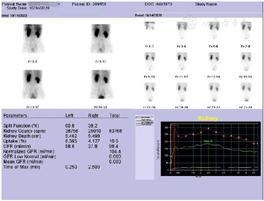

术后密切随访患者,2例患者术后影像学检查:

病例1: 2020年10月14日肾核素显像ECT组套(肾动态+肾小球滤过率),(图9)。